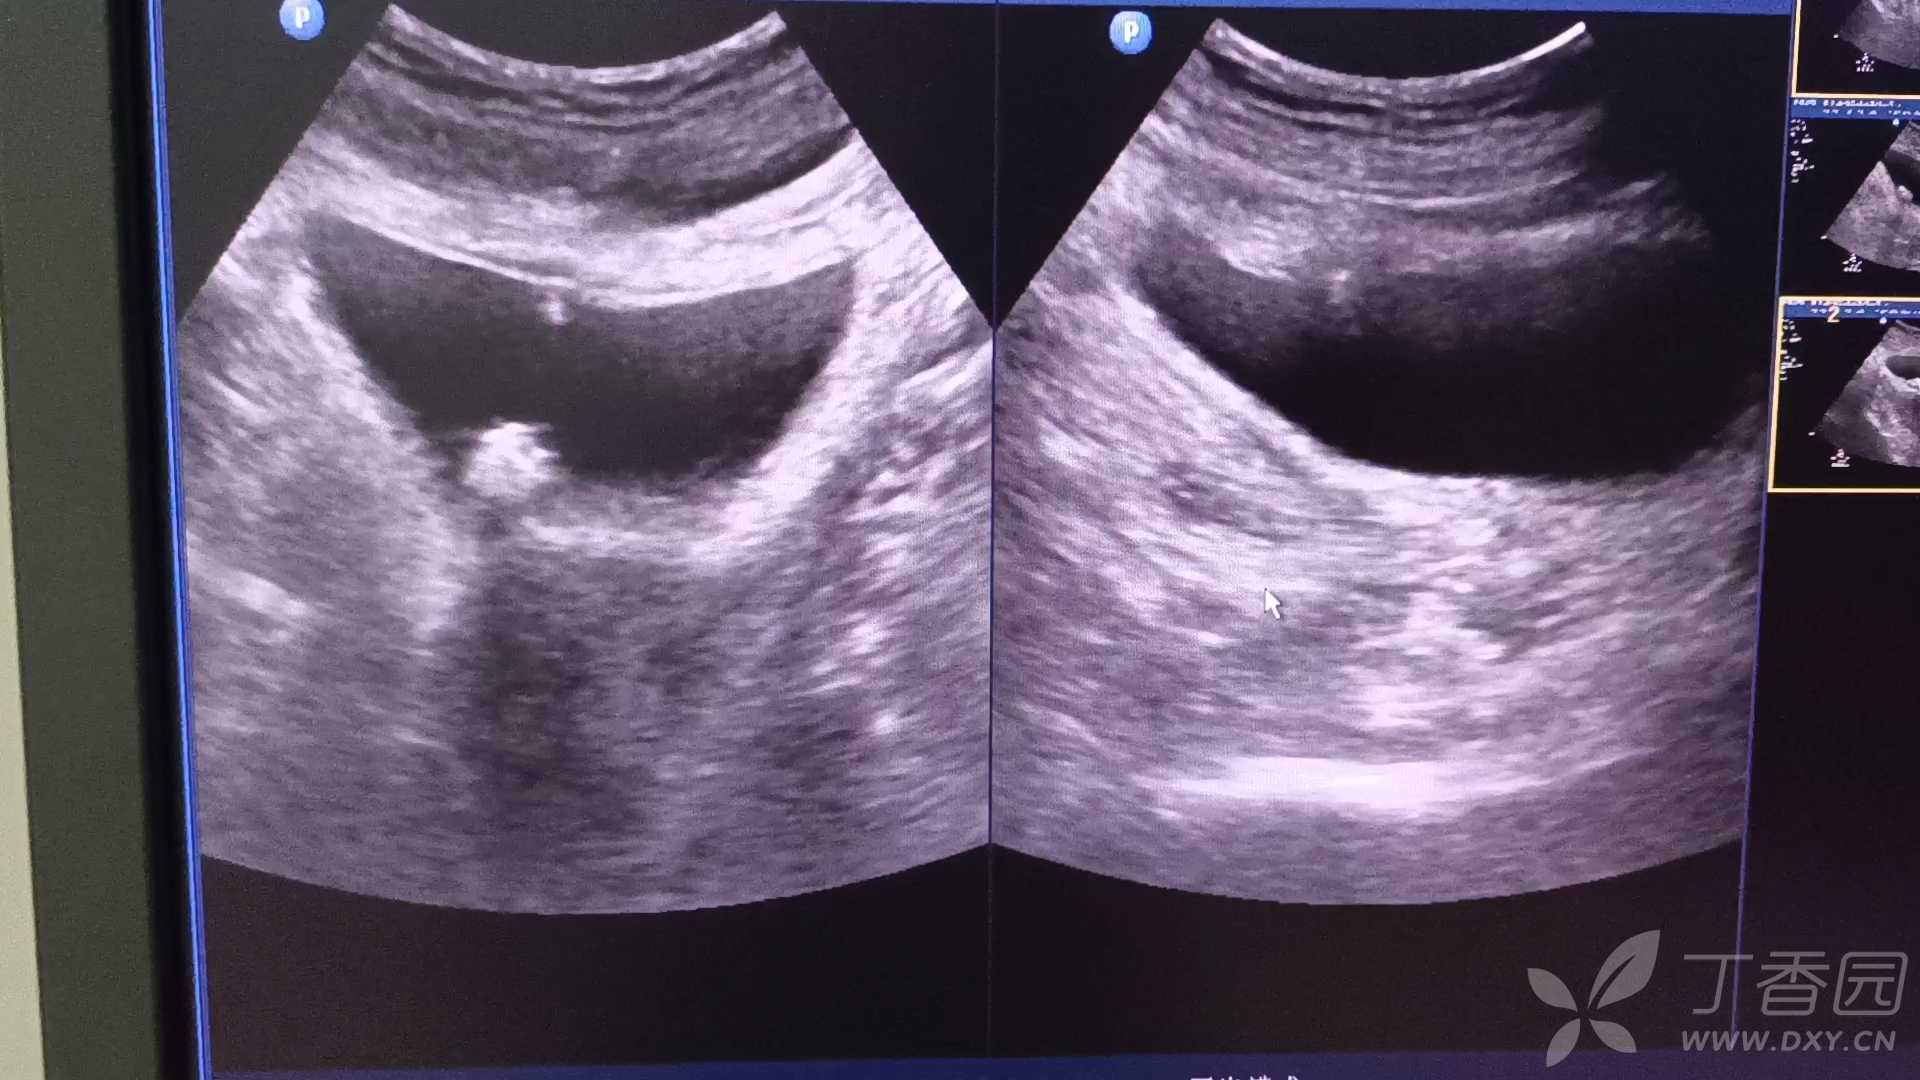

病例病理报告膀胱软斑症,复查超声所见,第一次听说此病

超声科医师 · 发布于 2021-11-15 · 来自 Android · IP 江西江西